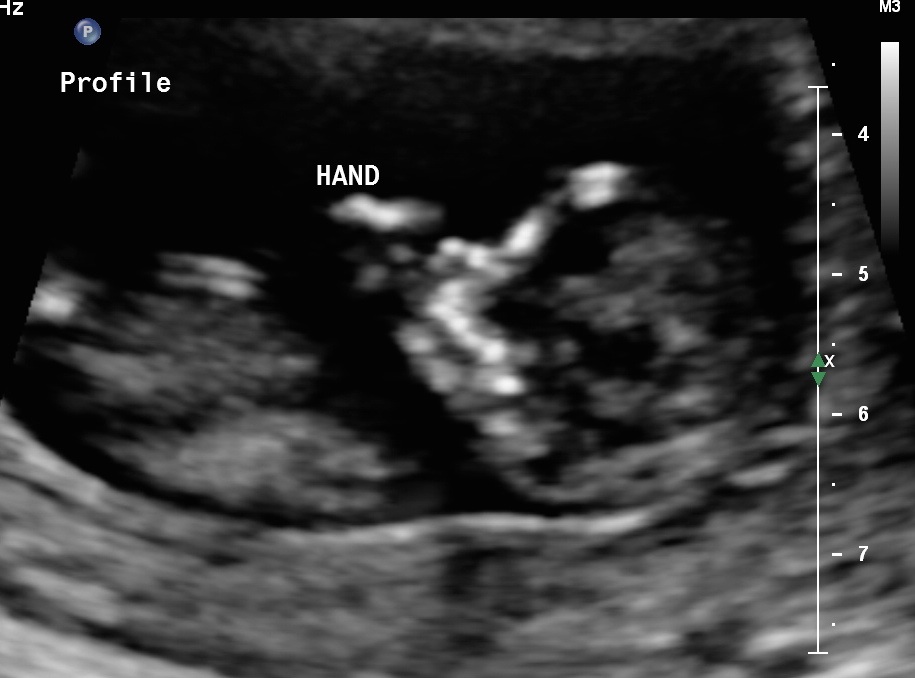

All went well. I posted a pic in the weekly check in. I have so many pics of our LO. Because everything went well, I made my pregnancy announcement on Facebook. Felt so good getting it out there. I'm adding my favorite pic here because it looks like the baby is puckering.

awwww kisses to you mama!!! So excited for mine!!!! Seeing everyone's reaction to it makes me so anxious!

image

• @kristieandjason2010

That is so awesome very cute pic! glad everything went well.